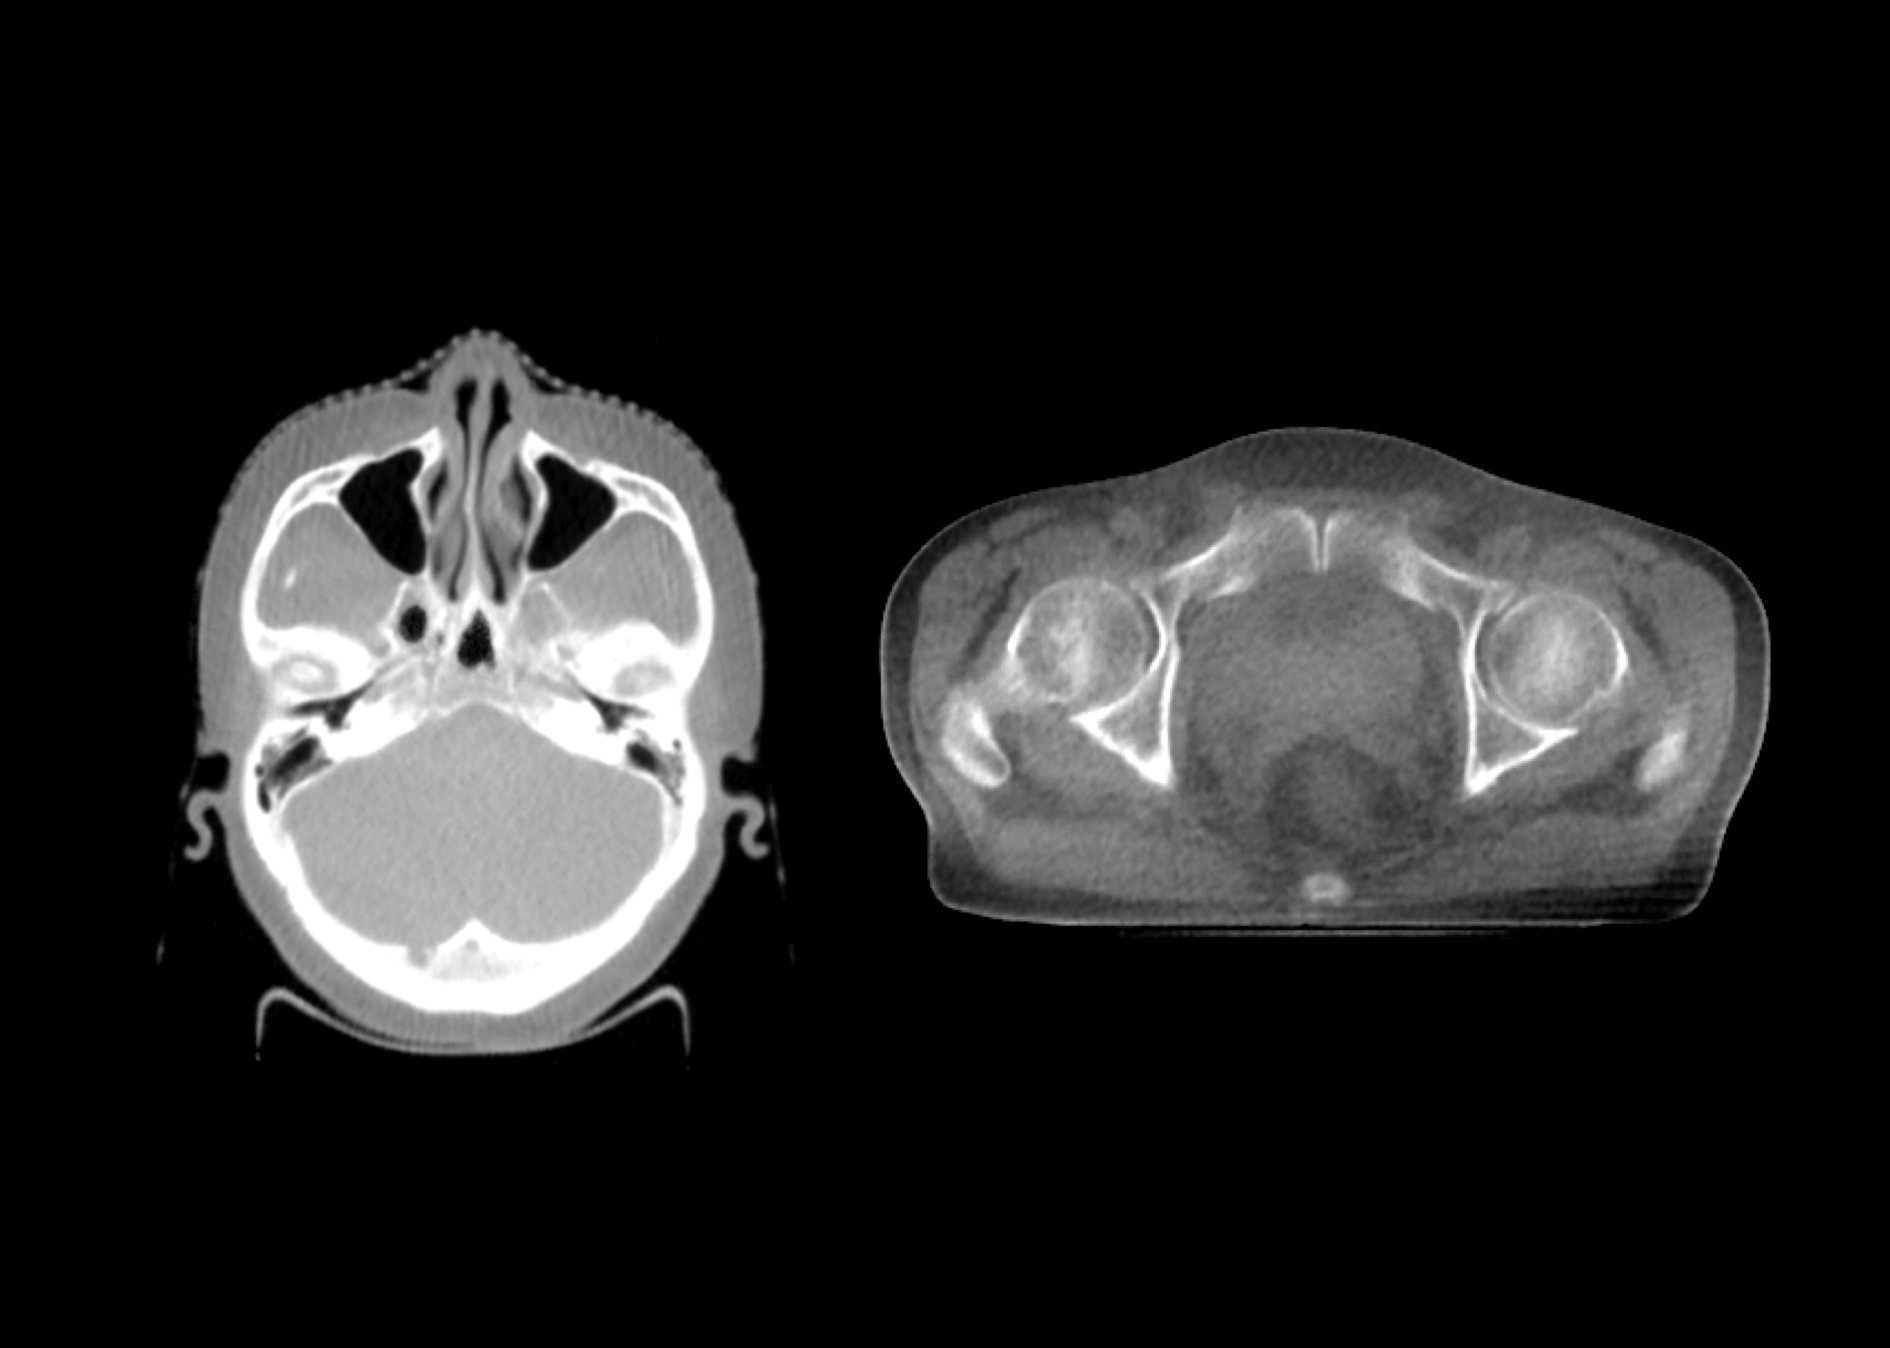

深度调能类kV级CBCT图像

类kV级成像

1.5MeV电子束打靶,使得千伏级成像光子占比更大,图像质量媲美常规kV级CBCT。

同源双束,高引导精度

影像引导成像束流与治疗束流同一等中心,带来更高的图像引导精度。